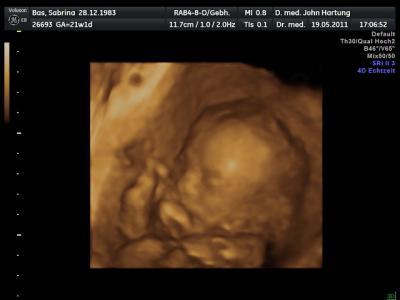

wie schon gestern vermutet die Nase von meinem Mann Meine Kinder haben alle eine kleine süße Stubsnase. Es bleibt eindeutig bei einem Mädchen. ich bin sooo happy. Meiner Maus geht es super. Sie studiert immer noch fleißig ihren ersten Tanz ein. Meine kleine ist 23 cm groß und wiegt 373g. Darf ich vorstellen meine kleine süße Maus Taliya !!!

Bild zu zurück von der FD uuund.... - Forum für September - Mamis